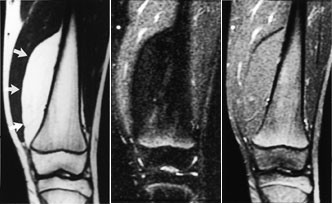

Bløtvevssvulster

Konvensjonelle røntgenbilder er første trinn i utredningen av mistenkte bløtvevssvulster (12). De viser underliggende skjelettdeformitet, beinaffeksjon og bløtvevsforkalkninger. Forkalkninger kan ikke påvises med MR. MR er allikevel den beste metoden, fordi den i tillegg til å vise de anatomiske forhold også fremstiller væske, nekrose, blødning, fett og annet bløtvev (fig 6 – 8). Basert på vekstmønster og signalforhold kan vevsspesifikk diagnose stilles i 20 – 40 % av tilfellene. Det er oftest ikke mulig å angi om en bløtvevstumor er benign eller malign. Nekrose er den enkeltfaktor som sterkest peker i retning av malignitet. Andre faresignaler er stor tumor, uskarp avgrensning med omgivende ødem, heterogent signal og beinaffeksjon. Men høymaligne bløtvevssvulster kan være velavgrenset med en pseudokapsel.